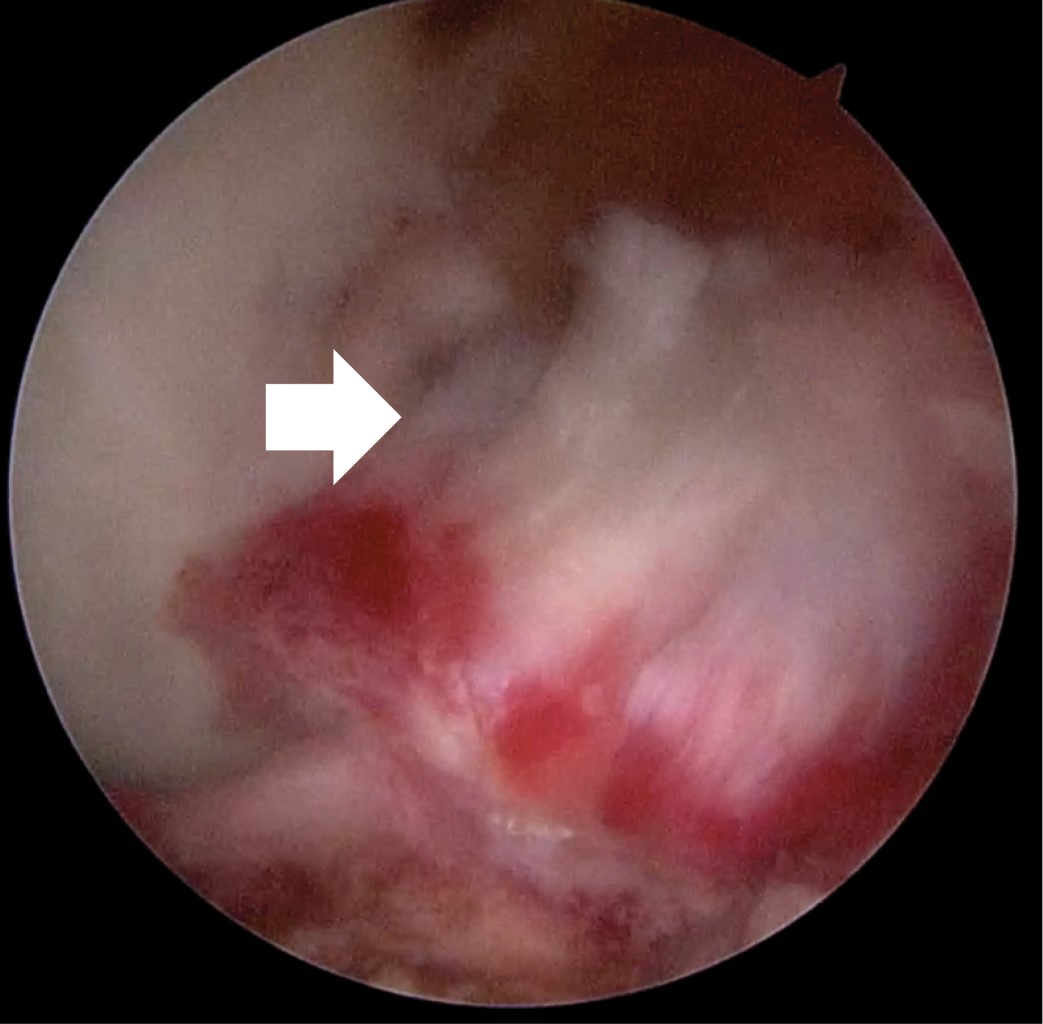

Introduction: Anterior cruciate ligament injuries are common, however, tibial avulsions in adults are rare. The gold standard continues to be reconstruction either by allograft or autologous graft. Primary repairs in femoral side lesions have been reported in recent years by bioabsorbable anchors. Case report: We present the case of a primary repair of anterior cruciate ligament due to tibial avulsion in a patient 19 years after presenting direct trauma with added lesions of posterior cruciate ligament and posterolateral corner. Primary repair was performed by trans-tendon portal with suture of the anterior cruciate ligament crossed by FiberTape and FiberWire with a SwiveLock anchor (4.75 mm) in tibial footprint. Results: Twelve months after surgery is with independent gait, full range of movement, with clinical rating scales, Tegner before injury and post-injury at 6, Lysholm 91, 73.6 subjective IKDC, objective IKDC in C and EQ-5D 0.79. Conclusion: Fixation with bioabsorbable anchor is possible in the avulsion of the post-traumatic tibial spine.

Figure 3